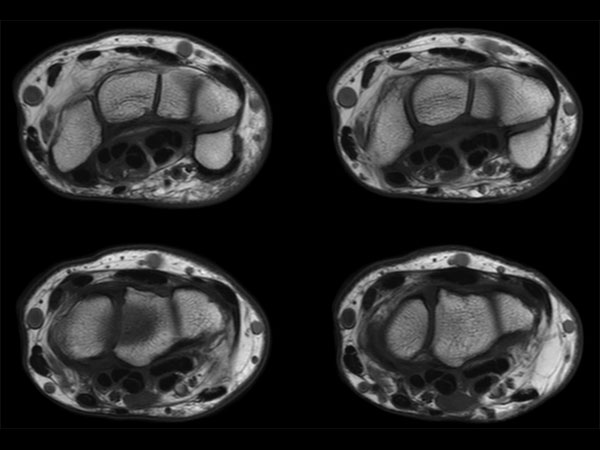

Wrist Imaging

Comprehensive Wrist imaging